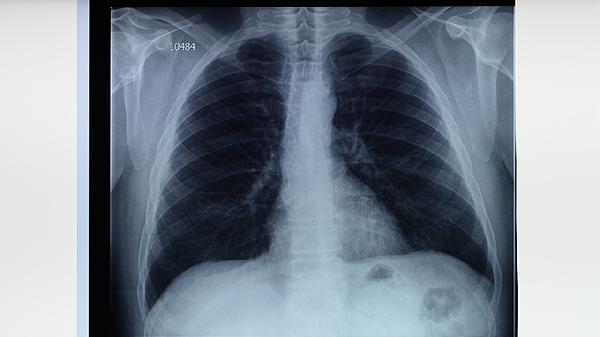

肺結(jié)核患者可以適量吃蘋果、梨、香蕉、獼猴桃、橙子等水果,有助于補(bǔ)充營養(yǎng)和增強(qiáng)免疫力。肺結(jié)核是由結(jié)核分枝桿菌感染引起的慢性傳染病,患者需在醫(yī)生指導(dǎo)下規(guī)范用藥,同時注意飲食調(diào)理。

肺結(jié)核患者應(yīng)保證充足的熱量和優(yōu)質(zhì)蛋白攝入,每日飲水1500-2000毫升。飲食宜清淡易消化,避免辛辣刺激食物。適當(dāng)進(jìn)行散步等輕度運(yùn)動,但避免劇烈活動。保持居室通風(fēng)良好,陽光充足。嚴(yán)格遵醫(yī)囑完成6-9個月規(guī)范治療,不可自行停藥。定期復(fù)查胸部X線或CT,監(jiān)測肝功能等指標(biāo)??人試娞鐣r注意遮掩口鼻,痰液需消毒處理。保證每日7-8小時睡眠,保持樂觀心態(tài)有助于康復(fù)。